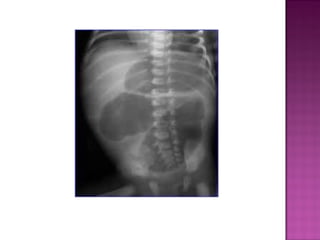

 AXR—gas filled stomach without distal

intestinal air. SINGLE BUBBLE SIGN.

 Rare  Usuallydistal  AXR—gas filled stomach without distal intestinal air. SINGLE BUBBLE SIGN.  Can be dx antenatally on ultrasound.